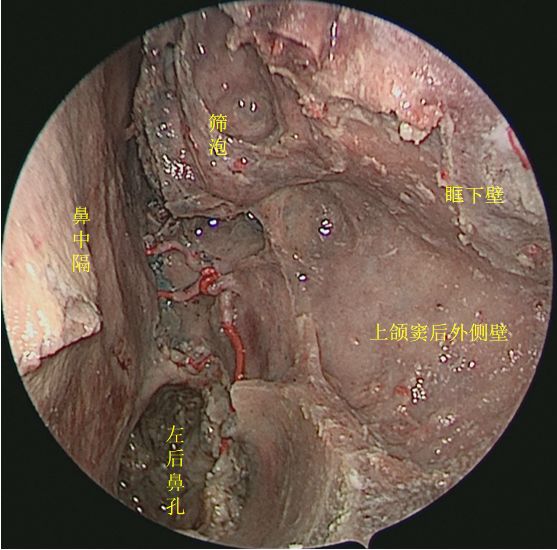

切除中鼻甲后观察鼻腔内整体空间形态

↑ 去除鼻中隔、左侧鼻腔侧壁结构及左眶内容物,前方观察各副鼻窦位置毗邻

↑ 去除鼻中隔观察鼻腔后壁结构

抵近观察左侧右鼻孔 ↓